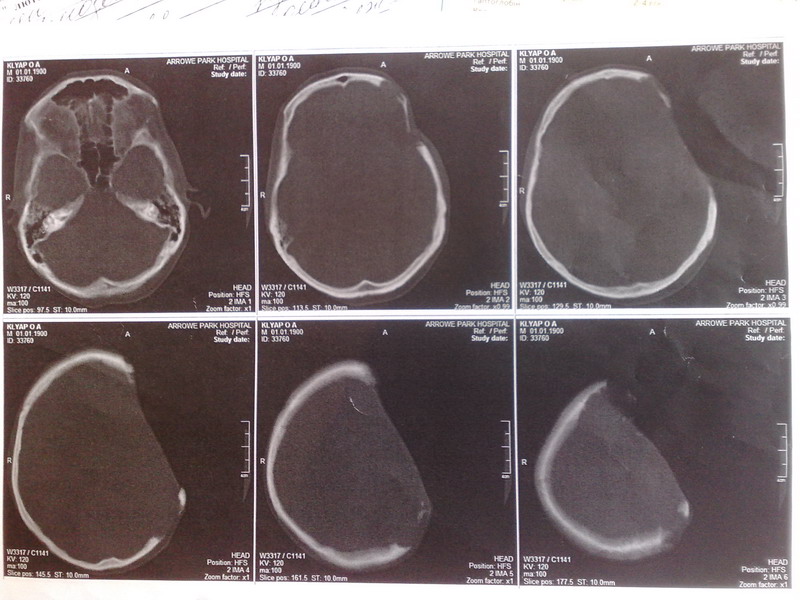

Больной 30 лет. Есть у него жена и дети. Ситуация состоит в том что у нас нет возможности

прооперировать больного из за того что больной материально не в состоянии оплатить

столь дорогой метод лечения. Речь идет за обласную больницу. Поскольку уже ранее используемый метод лечения протокриловым трансплантантом

уже применить нельзя поскольку большой дефект кости. Ранее у больного была опухоль костей

черепа - солитарная плазмоцитома. Которая была удалена. Дефект был замещен протокриловым трансплантантом. Со временем произошло его отторжение.

За последний год дефект немного увеличился. Несколько дней назад было сделано КТ на котором

поражения головного мозга не обнаружено. Додаю результаты КТ.